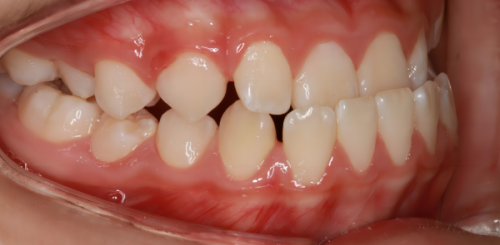

患者的反馈是检验一家口腔诊所好坏的重要标准。在上海丁士德口腔诊所,众多患者给出了好评。有的患者表示,在这里做牙齿矫正后,不仅牙齿变整齐了,自信心也提升了;还有的患者称赞医生治疗龋齿时手法轻柔,几乎没有疼痛感。这些真实的患者反馈,充分证明了该诊所的实力和口碑。